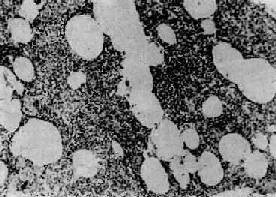

图9-15 大叶性肺炎

肺泡腔内充满纤维素性渗出物,纤维素丝穿过肺泡间孔,使相邻肺泡内的纤维素网互相连接